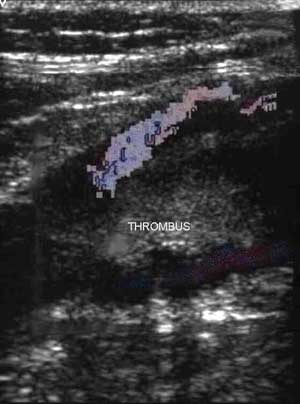

The main test used to exclude or diagnose DVT is Duplex ultrasound scanning. This is a simple, painless test with a high degree of accuracy. Ultrasound can demonstrate clot within the deep veins. It is particularly accurate in the larger veins of the leg. The image on the left is an ultrasound scan showing thrombus (the blood clot) with some blood flowing around the clot.